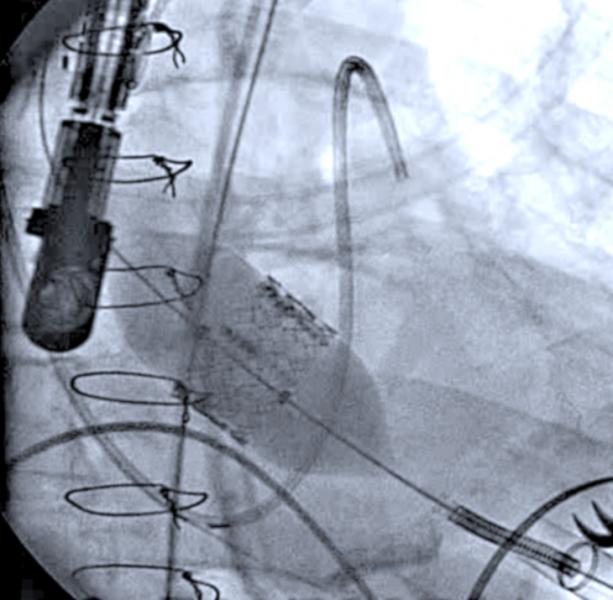

June 20, 2012 — Echocardiography is playing a key role in both the assessment and guidance of transcatheter aortic valve replacement (TAVR). Attendees at the American Society of Echocardiography’s 23rd Annual Scientific Sessions will have the opportunity to see this in action during a live TAVR procedure transmitted from Washington Hospital Center's hybrid cath lab.